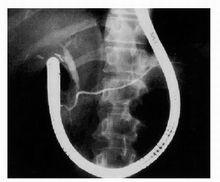

圖4:ERCP顯示在胰腺分裂中,通過付乳頭造影見典型的正常背側胰管,注意到內鏡呈未拉直狀態。